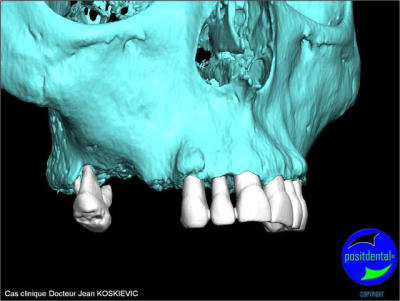

rendu 3D maxillaire sup, pano et photo

3D maxillaire inférieur et photo